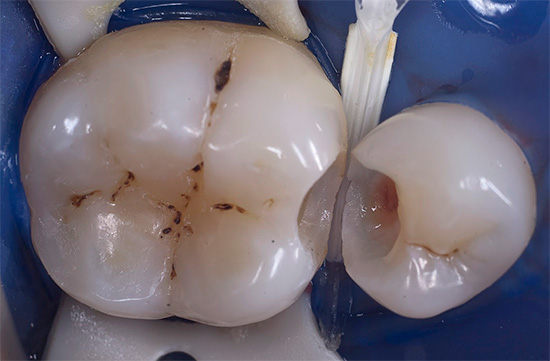

La fotografia sotto mostra un esempio di una cavità già formata durante il trattamento della carie profonda: